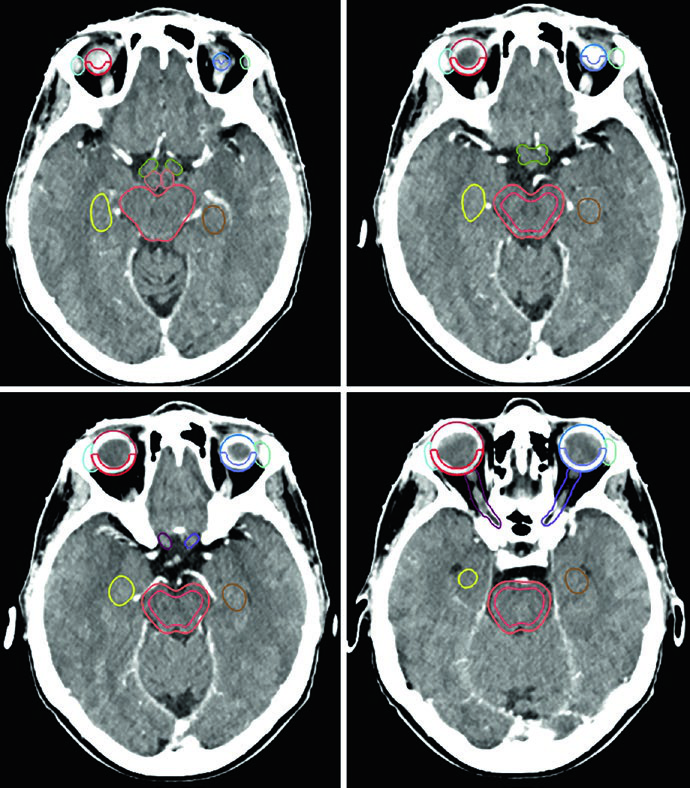

A lista de estruturas normais a contornar é extensa e reflete a sensibilidade das estruturas vizinhas. Para a maioria dos tumores benignos do SNC, o conjunto de OARs inclui: encéfalo total, encéfalo não envolvido (encéfalo menos GTV ou CTV), tronco encefálico dividido em core e superfície (rind de 3 mm), medula espinhal, cócleas direita e esquerda, globos oculares, cristalinos, nervos ópticos, quiasma, retinas, glândulas lacrimais, lobos temporais, hipocampos e hipotálamo. Volumes de risco planejado (PRVs) podem ser criados para tumores adjacentes a estruturas críticas, auxiliando na dosimetria e na avaliação do plano.

Cada OAR tem uma janela de visualização preferida. O tronco encefálico, quiasma óptico e componentes intracranianos dos nervos ópticos são melhor visualizados em janela cerebral. Os nervos ópticos nos canais ópticos e seus componentes orbitários ficam mais nítidos em janela de partes moles. As cócleas, por sua vez, só são identificadas com precisão em janela óssea. Já o hipocampo — especificamente a zona subgranular — é delineado em T1 de RM e visualizado na TC como substância cinzenta hipointensa, do nível do esplênio do corpo caloso superiormente até a extensão inferior do corno temporal do ventrículo lateral.

Um ponto prático crucial: a avaliação da TC é essencial para decidir se alterações periosteais e ósseas devem ser incluídas no GTV. No exemplo do meningioma do seio cavernoso (Figura 29.7), o tumor foi delineado com RM de planejamento, recebeu margem de 2 mm para o PTV e foi tratado a 52,2 Gy em 29 frações. As linhas de isodose mostram conformação apertada ao redor do tronco encefálico, quiasma, nervos cranianos adjacentes, artéria carótida e cóclea.

Meningiomas volumosos selares e suprasselares com ressecção incompleta — como na Figura 29.8 — podem requerer expansão de PTV de 3 mm por causa da doença residual extensa. A relação íntima com os globos e o tronco encefálico exige planejamento dosimétrico cuidadoso, frequentemente com IMRT ou VMAT para conformar a dose e proteger essas estruturas.